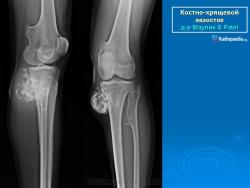

Локализация остеохондромы: частота поражения отдельных костей различна; нижний коней бедренной кости, верхние отделы плечевой и большеберцовой костей поражаются более чем у половины больных. На всем протяжении остеохондрома покрыта надкостницей. Она может быть обнаружена и в других костях, за исключением костей лицевого черепа. Все же поражение костей позвоночника, кистей рук и стоп встречается редко. При рентгенологическом исследовании видна типичная картина узкого или широкого выроста вблизи эпифизарной части пораженной кости. Обычно плотность узла неоднородная, имеются многочисленные плотные участки, соответствующие обызвествленным хрящевым долькам. Хрящевая «шапочка» большей частью не определяется, поскольку хрящ остается необызвествленным. Она может быть выявлена только при магнитно-резонансной томографии.